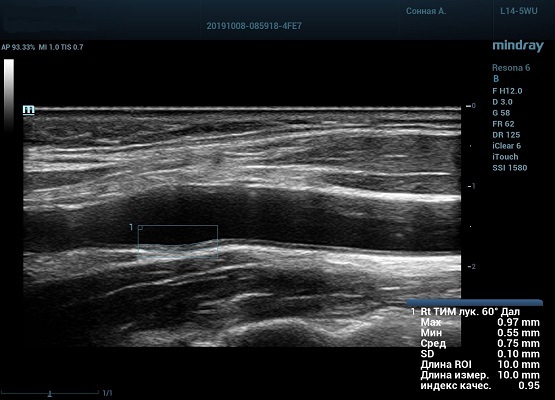

На сегодняшний день измерение IMT происходит автоматическим путем при использовании функции AUTO-IMT. Необходимо указать прибору зону интереса, стандартной длиной (1 см), в которой происходит отслеживание кромок и выдача максимального, среднего и минимального значения. УЗИ аппараты компании Mindray среднего, экспертного и премиального класса снабжены данной функцией и позволяют контролировать не только полученные значения, но и оценить точность измерения кромки в конкретной зоне по индексу качества. Используя индекс качества, легко решить, можно ли использовать полученное значение.

Также данный параметр используется для диагностики гипертензивной и атеросклеротической ангиопатии. Методика включает в себя измерение IMT проксимального, среднего и дистального отдела общей сонной артерии, каротидной луковицы, проксимального и среднего отдела внутренней сонной артерии. Далее вычисляем среднее значение и сравниванием с критериями Intima-mediathickness: Appropriate evaluation and proper measurement (ESC 2015, EAUD 2019) по центильной системе с привязкой к полу и возрасту.